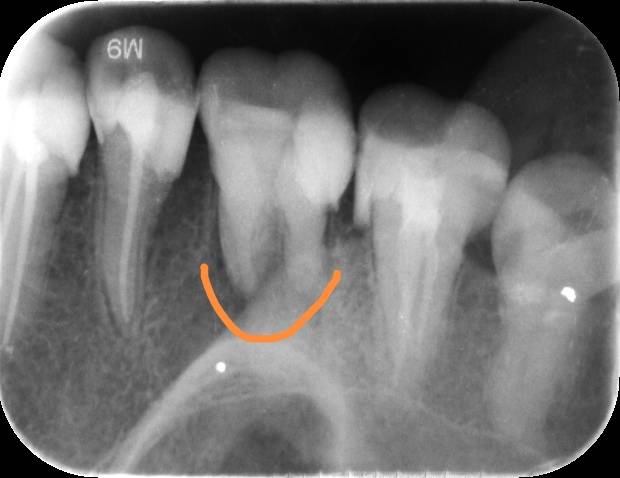

根管治疗

又有一颗牙晃动,看了医生说根管坏了,要做治疗。

做吧,去年11月刚做完一颗牙,我说很疼,医生说不疼,你这颗牙根管神经己坏死,不疼了。

今天消炎,一周后再去。